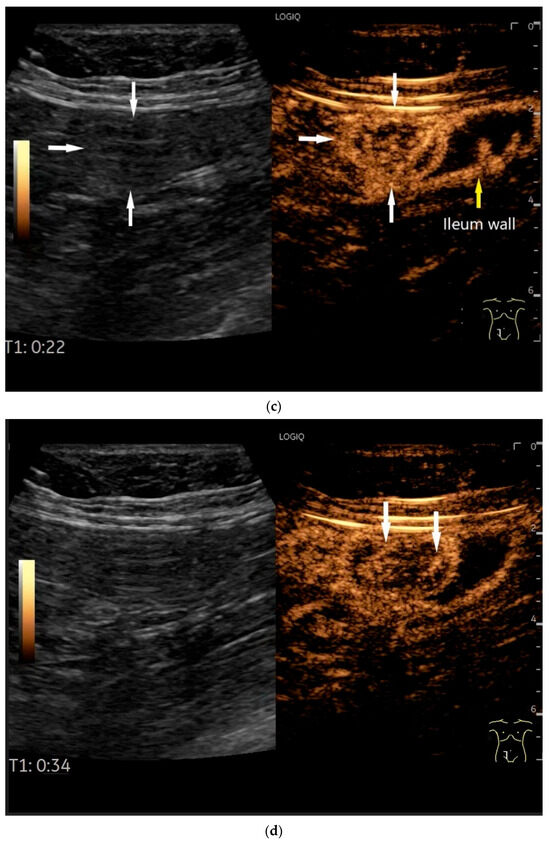

Figure 7.

NET in the ileum. An oval polyp-like lesion is visible in the ileum (a). Small vessels are visible on power Doppler, indicating that the tissue is solid (b). In CEUS with 2.4 mL SonoVue (linear transducer 2–9 MHz), the tumor capsule shows enhancement. The tumor is marked with white arrows. At 22 s, vessels can be distinguished in the tumor, but there is no complete enhancement of the tumor. The ileum wall is also enhanced (yellow arrow) (c). Even at the end of the arterial phase at 34 s, the tumor is not completely enhanced. Two macro vessels are marked with an arrow. Distally, they show irregular vessel branches (d). The tumor was not located directly behind the ileocecal valve. Based on the US findings, the endoscope was inserted 20 cm into the terminal ileum, where the tumor was then discovered.